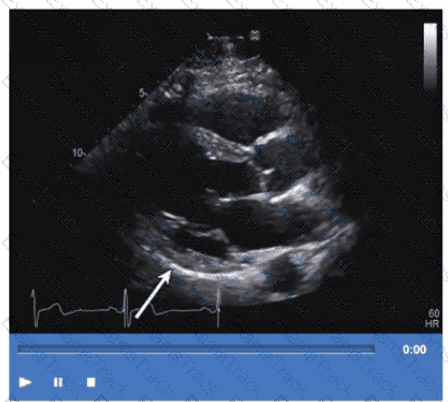

Which wall is indicated by the arrow on this video?